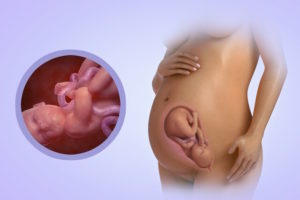

Чтобы выяснить, как развивается тошнота, если срок беременности 34 неделя, рекомендуется рассмотреть процессы, протекающие в женском организме на данном сроке.

Если пациентка лежит на спине, матка оказывает давление на крупную вену, замедляя процесс обращения крови.

При этом возникает обморочное состояние, появляется головокружение и тошнота. При подобной клинике рекомендуется лечь на бок.

На 34 неделе беременности женщина плохо спит, страдая от бессонницы, что также провоцирует приступы тошноты. Если у женщины 34 неделя беременности, она поправилась.Прибавка в весе нарушает координацию движений, провоцируя чувство неуклюжести. Из-за увеличенного живота появляется боль в спине, повышается подвижность суставов.

На 34 неделе в матке плоду становится тесно. При этом его активность высокий показатель, поэтому если появилась тошнота и вышеперечисленные симптомы, врач должен выяснить состояние плода.